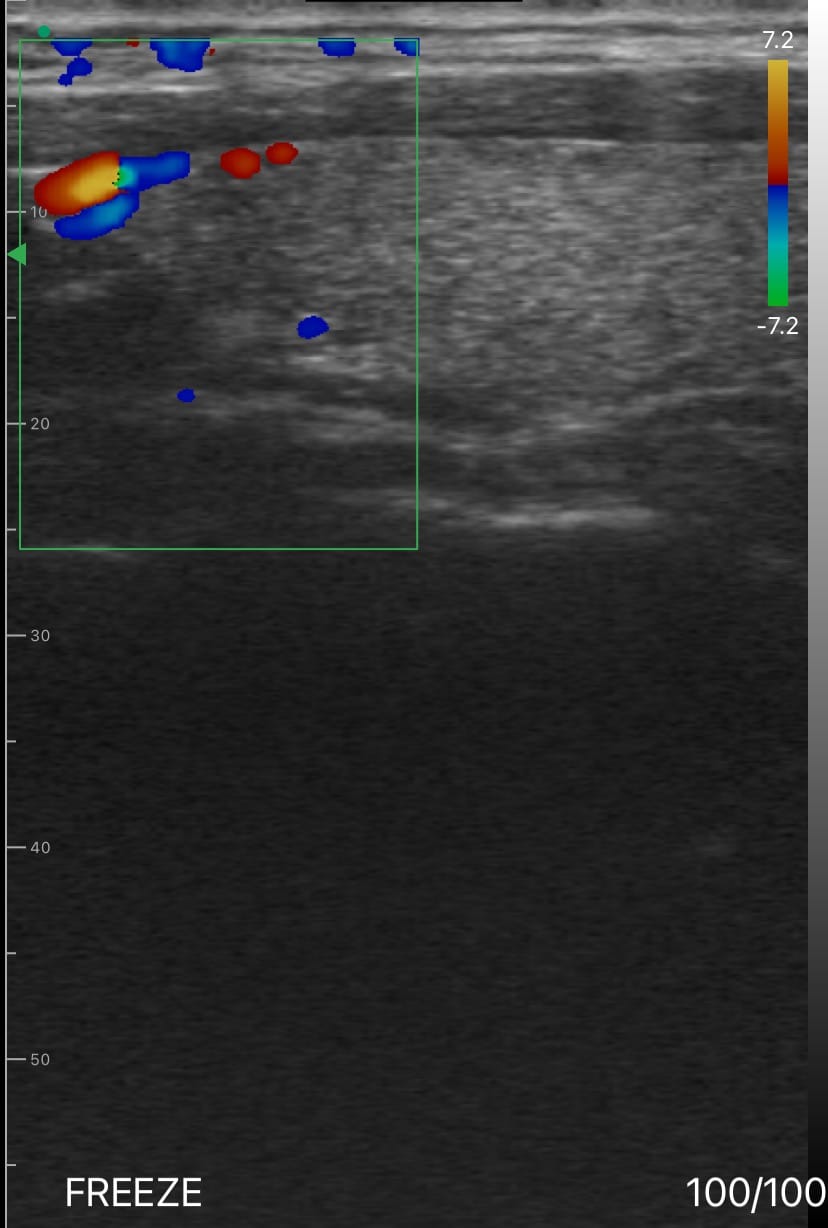

Upon examination, the thyroid nodule measured 1.8 cm and appeared isoechoic with well-defined margins, while the adjacent cyst measured 2.1 cm and exhibited anechoic characteristics with a thin, smooth wall. Color Doppler imaging revealed no significant blood flow in either the nodule or cyst, indicating that both lesions were stable and non-cancerous.